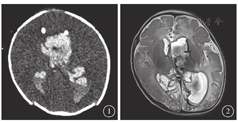

患儿男,1个月,出生胎龄39周,出生体重3350 g。既往史无特殊。2017年6月25日无明显诱因突发烦躁伴四肢抽动、偶有僵直,双眼向下凝视,安抚后不能缓解,急诊于外院;颅脑CT检查,脑室大量出血,蛛网膜下腔少量出血可能。遂转诊于我院,急诊行双侧脑室钻孔手术。次日复查头颅CT,诸脑室内积血铸型,左侧侧脑室扩张(图1)。手术后患儿意识尚清,对外界刺激反应正常。手术后1周,拔除引流管;颅脑MRI检查,左侧脑室及第三、四脑室可见明显血肿,双侧侧脑室扩张(图2)。遂改行双侧侧脑室穿刺外引流联合右侧储液囊植入手术。手术后患儿意识清楚,对外界刺激反应正常。2017年8月29日我科会诊,第三代儿童广角数码视网膜成像系统筛查,右眼玻璃体腔见黄白色团块状混浊,居于瞳孔区,透过混浊区可隐约见视盘,周边隐约见大片视网膜下出血,颜色暗(图3);左眼眼底未见明显异常。眼彩色超声检查,右眼玻璃体混浊。结合病史诊断:右眼Terson综合征(玻璃体积血、机化)。由于患儿脑脊液控制欠佳,无法行右眼玻璃体切割手术(PPV),暂予观察处理。观察2周后,右眼玻璃体混浊较前稀疏,呈白色絮状,隐约透见视盘,周边视网膜见末端血管及散在片状视网膜下出血,范围较前缩小(图4)。2017年9月27日,患儿颅内压控制稳定,转外院于全身麻醉下行右眼PPV。手术后2周回访,右眼视盘边界清晰,颜色淡红,视网膜平复,血管细,周边视网膜下出血已吸收,黄斑区反光弱(图5)。